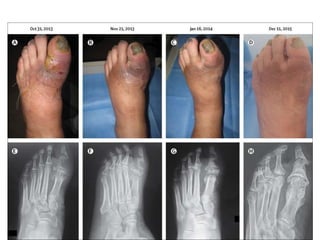

Chronic ulcer withstructural deformity

• 30.